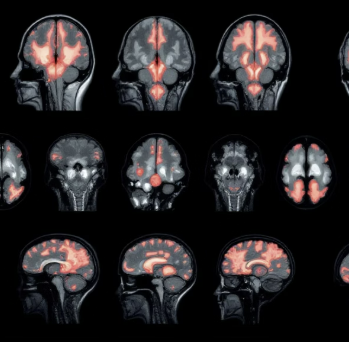

단계 영어 약자 증상 확인 조치 1 Face (얼굴) 웃어보라고 했을 때, 한쪽 얼굴이 처지는가? 확인 2 Arms (팔) 양팔을 앞으로 들었을 때, 한쪽 팔이 떨어지는가? 확인 3 Speech (말) 간단한 문장을 말하게 했을 때, 말이 어눌하거나 이상한가? 확인 4 Time (시간) 위 증상 중 하나라도 나타났다면 증상 발생 시각을 확인하고 즉시 119에 전화하세요! 즉시 119 신고! 응급실에서의 초기 치료: 병원에 도착하면 곧바로 CT 또는 MRI 촬영을 통해 출혈인지 경색인지 진단합니다. 진단 결과 뇌경색이며 골든타임 이내라면 혈전을 녹이는 약물(tPA)을 투여하거나, 막힌 혈관을 직접 뚫는 기계적 혈전 제거술을 시행하여 뇌졸중으로 인한 뇌 손상을 최소화합니다.